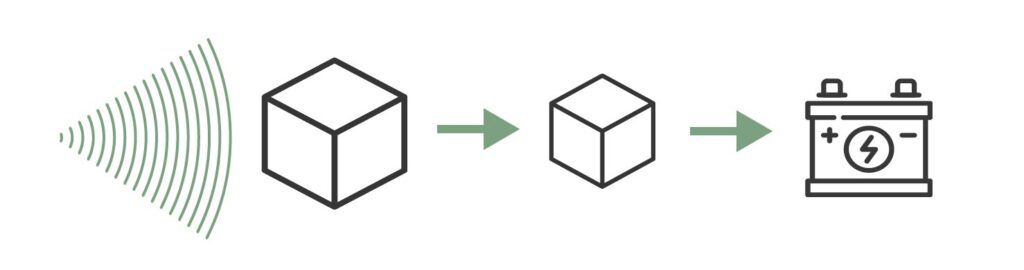

En el caso de los ultrasonidos, necesitaremos una fuente llamada cristal piezoeléctrico. Estos cristales tienen la propiedad de que, al recibir corriente eléctrica, se deforman y comprimen emitiendo ondas de muy alta frecuencia (los ultrasonidos), así como la inversa, generan un campo eléctrico al ser sometidos a deformación mecánica.

Emisión del ultrasonido

El cristal recibe electricidad, se deforma, y esa deformación produce el ultrasonido.

El ultrasonido viaja a través del medio (cuerpo del paciente) y genera ecos a medida que atraviesa el tejido, veremos más adelante cómo interacciona con el mismo.

Recepción del ultrasonido

El cristal recibe el eco del ultrasonido que ha enviado anteriormente, se deforma y genera un impulso eléctrico que puede detectarse.

En función de la intensidad del eco que impacta con el cristal se generan campos eléctricos de diferentes magnitudes que, mediante la informática, se pueden representar en un monitor y producen la imagen de ecografía tal y como la conocemos hoy en día.